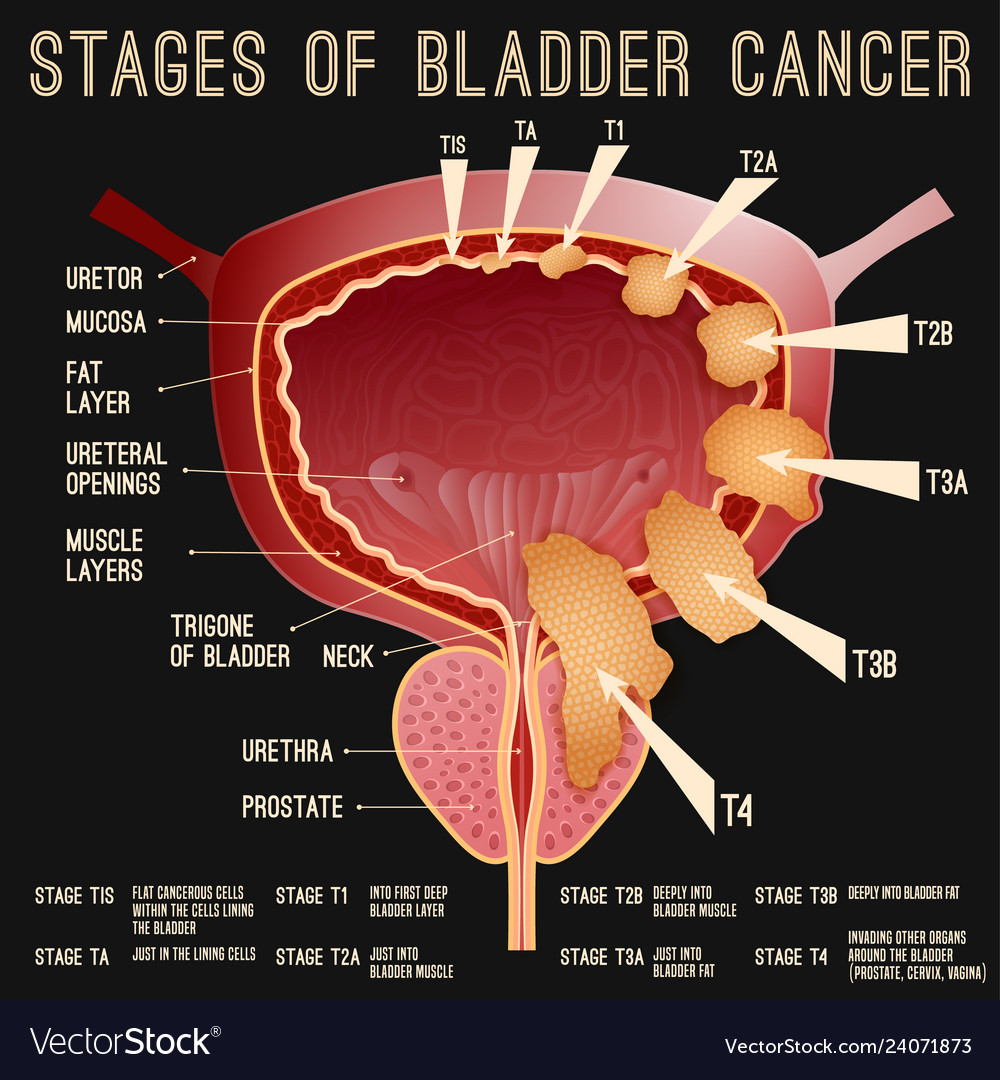

Bladder Cancer Stages Royalty Free Vector Image

https://cdn4.vectorstock.com/i/1000x1000/18/73/bladder-cancer-stages-vector-24071873.jpg